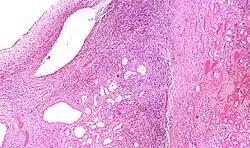

Micrograph of a cystic nephroma. H&E stain.

The characteristics of cystic nephromas are:

- Cysts lined by a simple epithelium with a hobnail morphology, i.e. the nuclei of the cyst lining epithelium bulges into the lumen of the cysts,

- Ovarian-like stroma that has a:

- Spindle cell morphology, and has a

- Basophilic cytoplasm.

Cystic nephromas have an immunostaining pattern like ovarian stroma; they are positive for:

- Estrogen receptor (ER),

- Progesterone receptor (PR) and

- CD10.